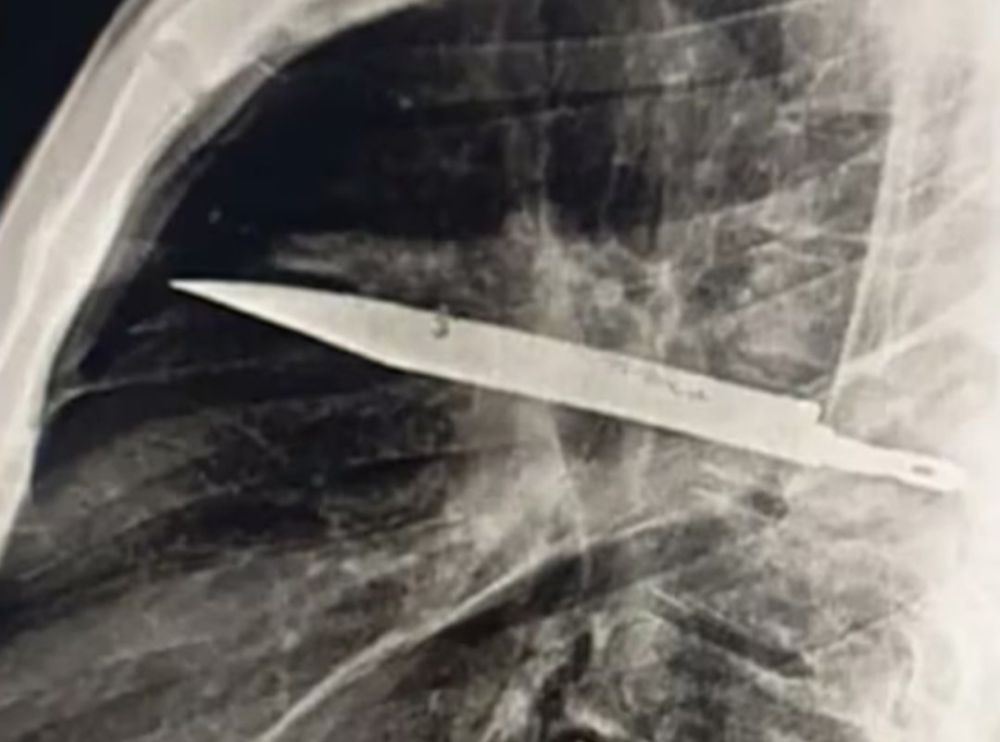

Um homem de 44 anos descobriu que carregava uma lâmina de faca em seu peito há oito anos. O objeto foi identificado após ele procurar atendimento médico devido a secreção no peito. Exames revelaram que a lâmina estava entre as costelas, sem atingir órgãos vitais. O fato aconteceu da Tanzânia.

Exames de raio-X revelaram que o corpo do paciente havia formado uma cápsula fibrosa ao redor da lâmina, o que isolou o objeto e evitou danos maiores. Após a descoberta, o paciente foi submetido a uma cirurgia para remoção da lâmina e drenagem da secreção.